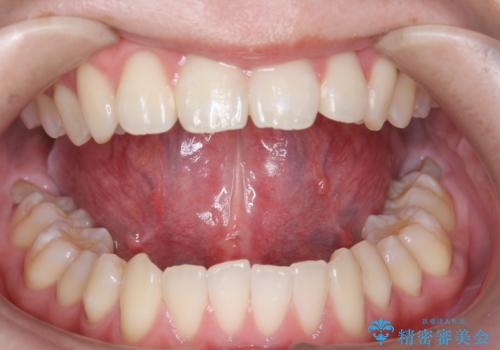

- 舌が動かしにくく、発音に支障があるため、舌小帯切除術を希望された方の症例です。

舌小帯は舌の下にある線維性のスジです。これが短かったり、強直していると、舌運動を上手く行えず、発音や咀嚼・嚥下等に弊害をきたす場合があります。

舌小帯を切除することで舌の可動域が広がり、上記の弊害を改善することが可能です。